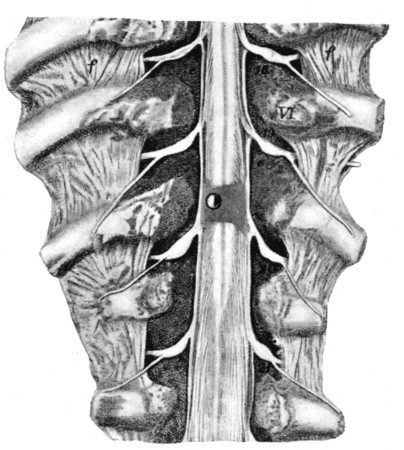

80. Divided Spinal Cord 334